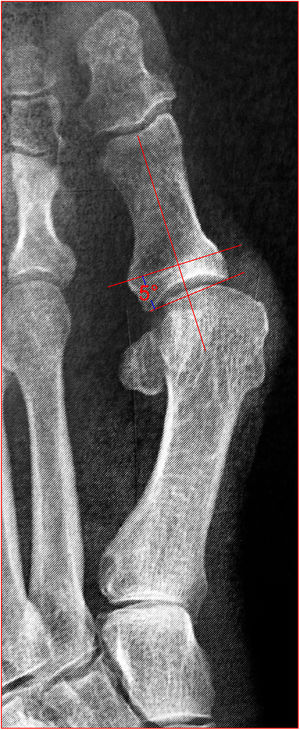

Angulo de desplazamiento articular distal (DASA por sus siglas en inglés), mide la orientación de la superficie articular de la falange proximal. Es el ángulo entre la perpendicular a la línea del eje de la falange proximal y la línea de la articulación de la falange proximal. Mayor a 10 indica deformidad en la falange (fig. 7).